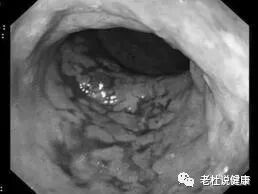

为进一步明确诊断,医生又为刘奶奶安排了肠镜检查。结果发现升结肠区管壁僵硬、管腔狭窄、糜烂出血,局部多发溃疡,覆白色粘液,血管网纹模糊;并见局部粘膜苍白、青紫;

最后确诊:缺血性肠病,也就是肠中风。